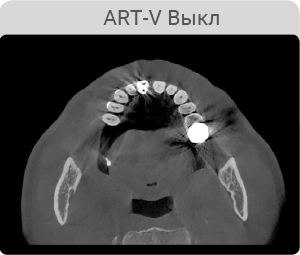

Технология ART-V - уменьшение артефактов

Артефакты от металлов мешают визуализации и естественным образом снижают достоверность диагностики. Четкие изображения дают вам меньше поводов волноваться и больше доверия к результатам диагностики при планировании имплантации. А также вам не составит труда планирование хирургического шаблона.

*ART-V новое название алгоритма коррекции артефактов от VATECH.